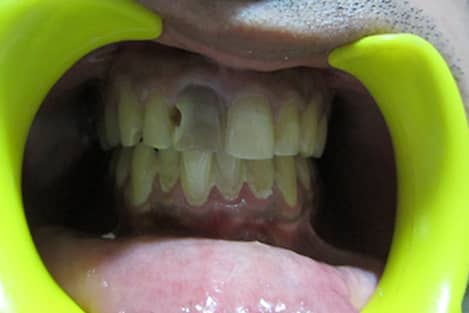

Non Vital Tooth Bleaching